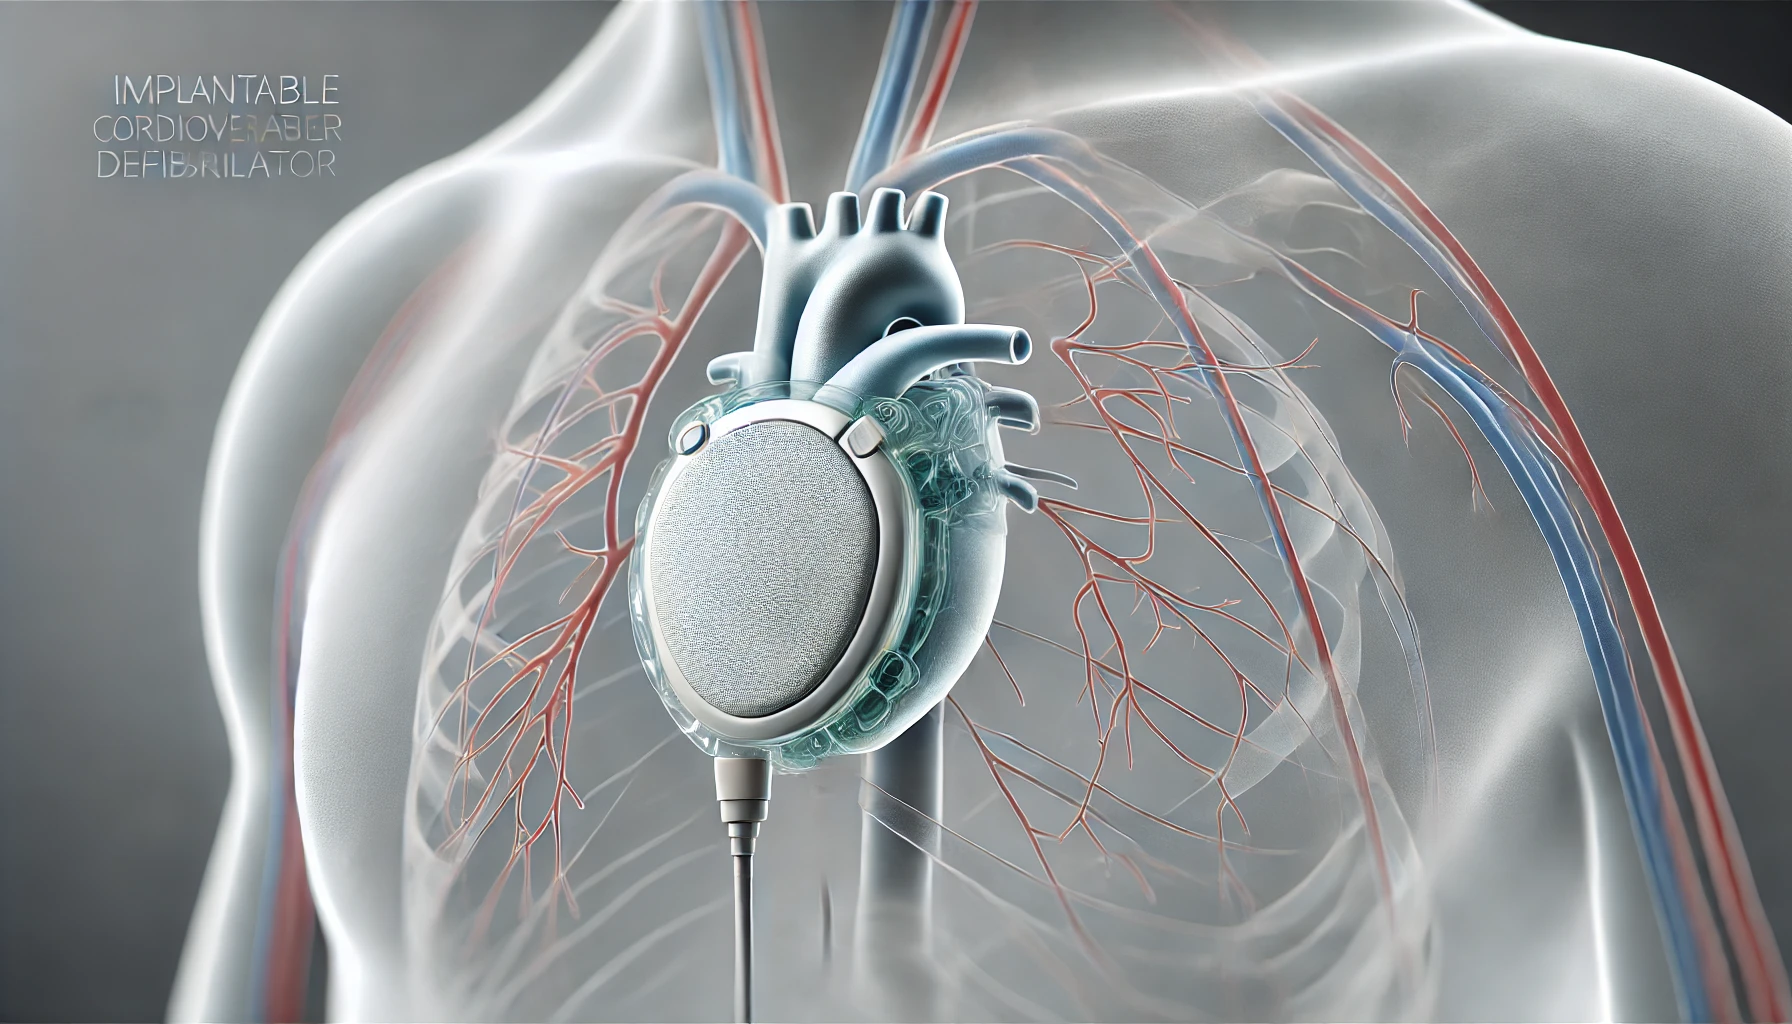

صحة و جمالفي خطوة مبتكرة تهدف إلى تحسين حياة مرضى القلب والكلى، كشفت شركة ناشئة كندية عن…